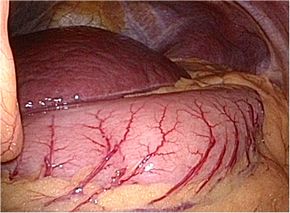

早期胃がんに対する低侵襲治療

胃がんに対する腹腔鏡下手術は、日本で1991年に開始され20年以上経過しています。

当院では内視鏡治療では切除しきれない、つまり胃がんの拡がりや胃の近くにあるリン

パ節をとる必要があると判断される早期胃がんに対して腹腔鏡下手術を行っております。

腹腔鏡下胃切除術の実際

全身麻酔下で手術を行います。まず腹腔内(腹腔:お腹の壁と臓器との間の空間)に炭酸

ガスを入れて膨らませ、お臍からカメラ(腹腔鏡)を挿入します。同時に手術操作に用い

る器具(鉗子など)を挿入するための5〜10mmの小さな穴を左右に4カ所開けます。そ

して腹腔鏡で撮ったお腹の中の様子をモニターに映し出して、胃切除や周囲のリンパ節

の切除を行います。開腹手術では見えにくかった細い血管や神経まで見えて繊細な手術

操作が可能です。